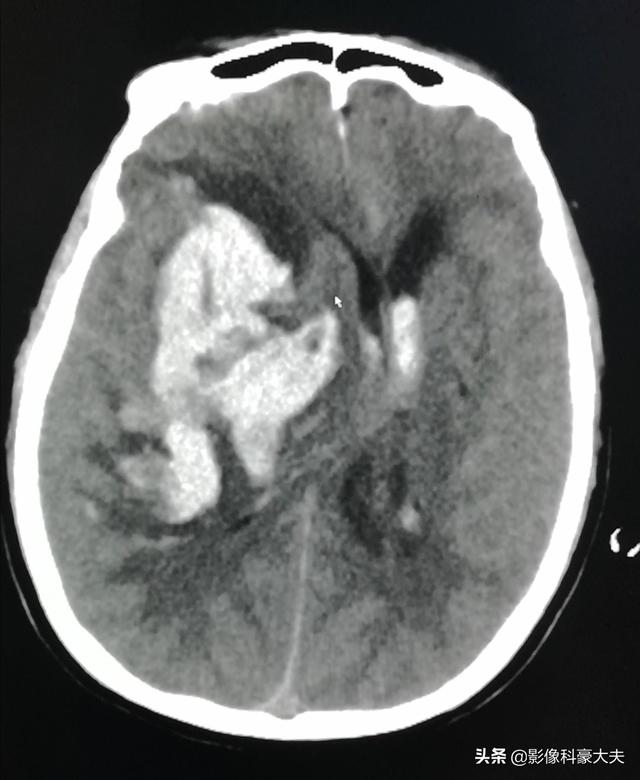

L'hémorragie sous-arachnoïdienne est principalement causée par des anévrismes intracrâniens et des malformations vasculaires cérébrales (spinales), qui représentent environ 70 % des hémorragies sous-arachnoïdiennes spontanées, suivis par l'artériosclérose hypertensive, la maladie tabagique et les maladies du sang. Le pronostic global de l'hémorragie sous-arachnoïdienne spontanée est mauvais et le taux d'invalidité des survivants est relativement élevé. La plupart des patients présentent un début rapide de la maladie, sans symptômes d'aura, se manifestant par des céphalées sévères, une photophobie, des nausées, des vomissements, une pâleur, des sueurs froides, parfois accompagnés d'épilepsie, de vertiges, de douleurs au niveau du cou et des épaules ou des membres inférieurs, et environ la moitié des patients présentent des symptômes mentaux, tels que l'agitation, la confusion, la désorientation, etc. Dans les cas graves, le patient peut tomber dans le coma, voire subir une hernie cérébrale et mourir. J'ai rencontré un patient de ce type, un garçon de 25 ans, entraîneur de fitness, qui a subi une rupture soudaine d'un anévrisme cérébral et une hémorragie, qui a été sauvé pendant longtemps, mais dont le pronostic est très sombre. La photo ci-dessous montre un patient souffrant d'une rupture d'anévrisme cérébral (flèche droite) et d'une hémorragie (zone blanche encerclée à gauche), ayant des antécédents d'hypertension, se disputant avec quelqu'un et s'effondrant soudainement sur le sol.